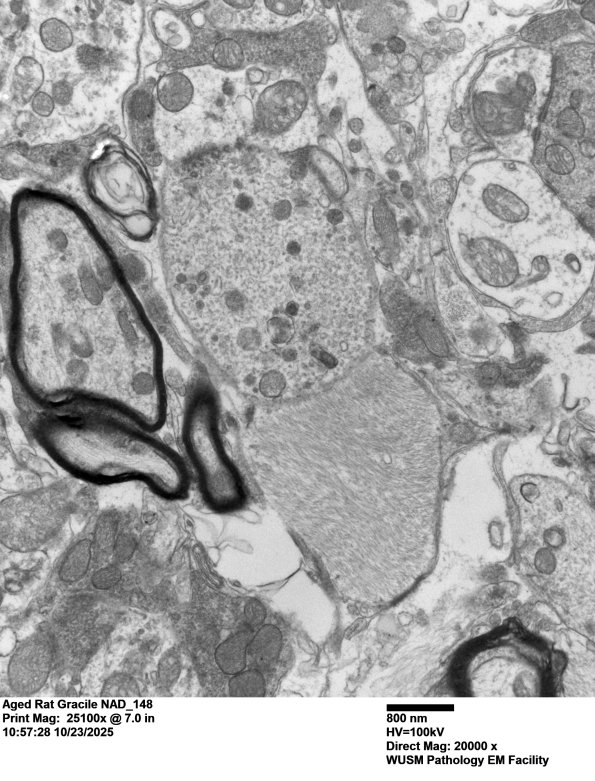

18O1,2 A small dystrophic terminal with synapses exhibiting synaptic vesicles and a postsynaptic density. (electron micrographs)